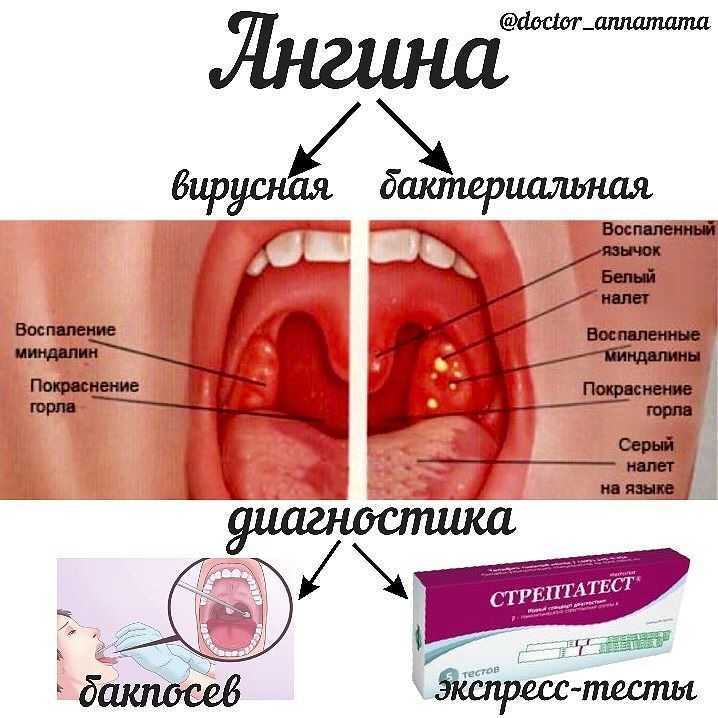

Клиническое течение при ангине у каждого ребенка может отличаться, учитывая тип заболевания:

Проявиться разные виды заболевания могут при воздействии на небные миндалины патогенных микроорганизмов – вирусов, бактерий, грибков. У детей младшего возраста ангина преимущественно имеет вирусное происхождение, проявляясь вследствие вируса герпеса, Эпштейн-Барра, аденовируса, цитомегаловируса. У школьников заболевание возникает при воздействии стрептококков, стафилококков, грибков, спирохет, пневмококков. Здоровый детский организм способен противостоять воздействию инфекции. Заболевание развивается при ослаблении иммунной системы на фоне переохлаждения, усиленных физических нагрузок, частых стрессов, несбалансированного питания, рецидивирующих респираторных заболеваний.

Виновниками гнойной ангины у детей наиболее часто бывают патогенные бактерии: стафилококки, пневмококки, диплококки, стрептококки и прочие. Вся эта микрофлора всегда присутствует в верхних дыхательных путях человека и, если в норме, не опасна для здоровья.

Болезнь возникает в том случае, когда повышается активность микроорганизмов, спровоцированная слабым иммунитетом, а также некоторыми вирусами, такими как аденовирус и грипп. Гнойная ангина чаще всего вызывается микробами, которые живут не только на слизистой оболочке горла, но и на миндалинах, вследствие чего после операции по удалению миндалин ангина практически невозможна.

Причины бактериальной ангины у детей

Бактериальная ангина представляет собой инфекционное заболевание, при котором возникает воспаление ткани небных миндалин в результате попадания на них патогенных микроорганизмов, либо увеличения числа условно-патогенных микроорганизмов. Они проникают воздушно-капельным путем от инфицированного человека к здоровому при кашле, чихании, при использовании одних и тех же столовых приборов, полотенец и др.

При проведении микробиологического исследования посева с поверхности миндалин выявляют следующих возбудителей тонзиллита:

- 30-40% бета-гемолитический стрептококк группы А;

- 28-30% стрептококки группы С и G;

- 20-25% стафилококки;

- 5-22% иные микроорганизмы: нейссерия, микоплазма, пневмококк и др.

Наиболее часто бактериальная или гнойная ангина у детей вызывается бета-гемолитическим стрептококком группы А. Причина заключается, прежде всего, в его строении: они несут капсулы (М-белок) для адгезии к слизистой оболочке миндалин. Эти микроорганизмы устойчивы к фагоцитозу и выделяют различные экзотоксины. Последние приводят к выработке антител, которые перекрестно действуют еще и на сердечную мышцу, ткань сосудов, суставов и почечную паренхиму.

Нужно чётко следовать всем рекомендация лечащего педиатра для скорейшего выздоровления малыша. Эффективное лечение ангины подразумевает обильный приём жидкости, жаропонижающих, антибиотиков, эубиотиков, антигистаминных средств, полоскания горла и витаминотерапии.

Но полоскание горла это только 1 из вспомогательных способов, т. к. основное лечение заключается в приёме антибактериальных средств

Один из способов лечения ангины — это полоскание горла для детей старшего возраста и обработка аэрозолями и спреями маленьких детей. Но полоскание горла это только 1 из вспомогательных способов, т. к. основное лечение заключается в приёме антибактериальных средств.